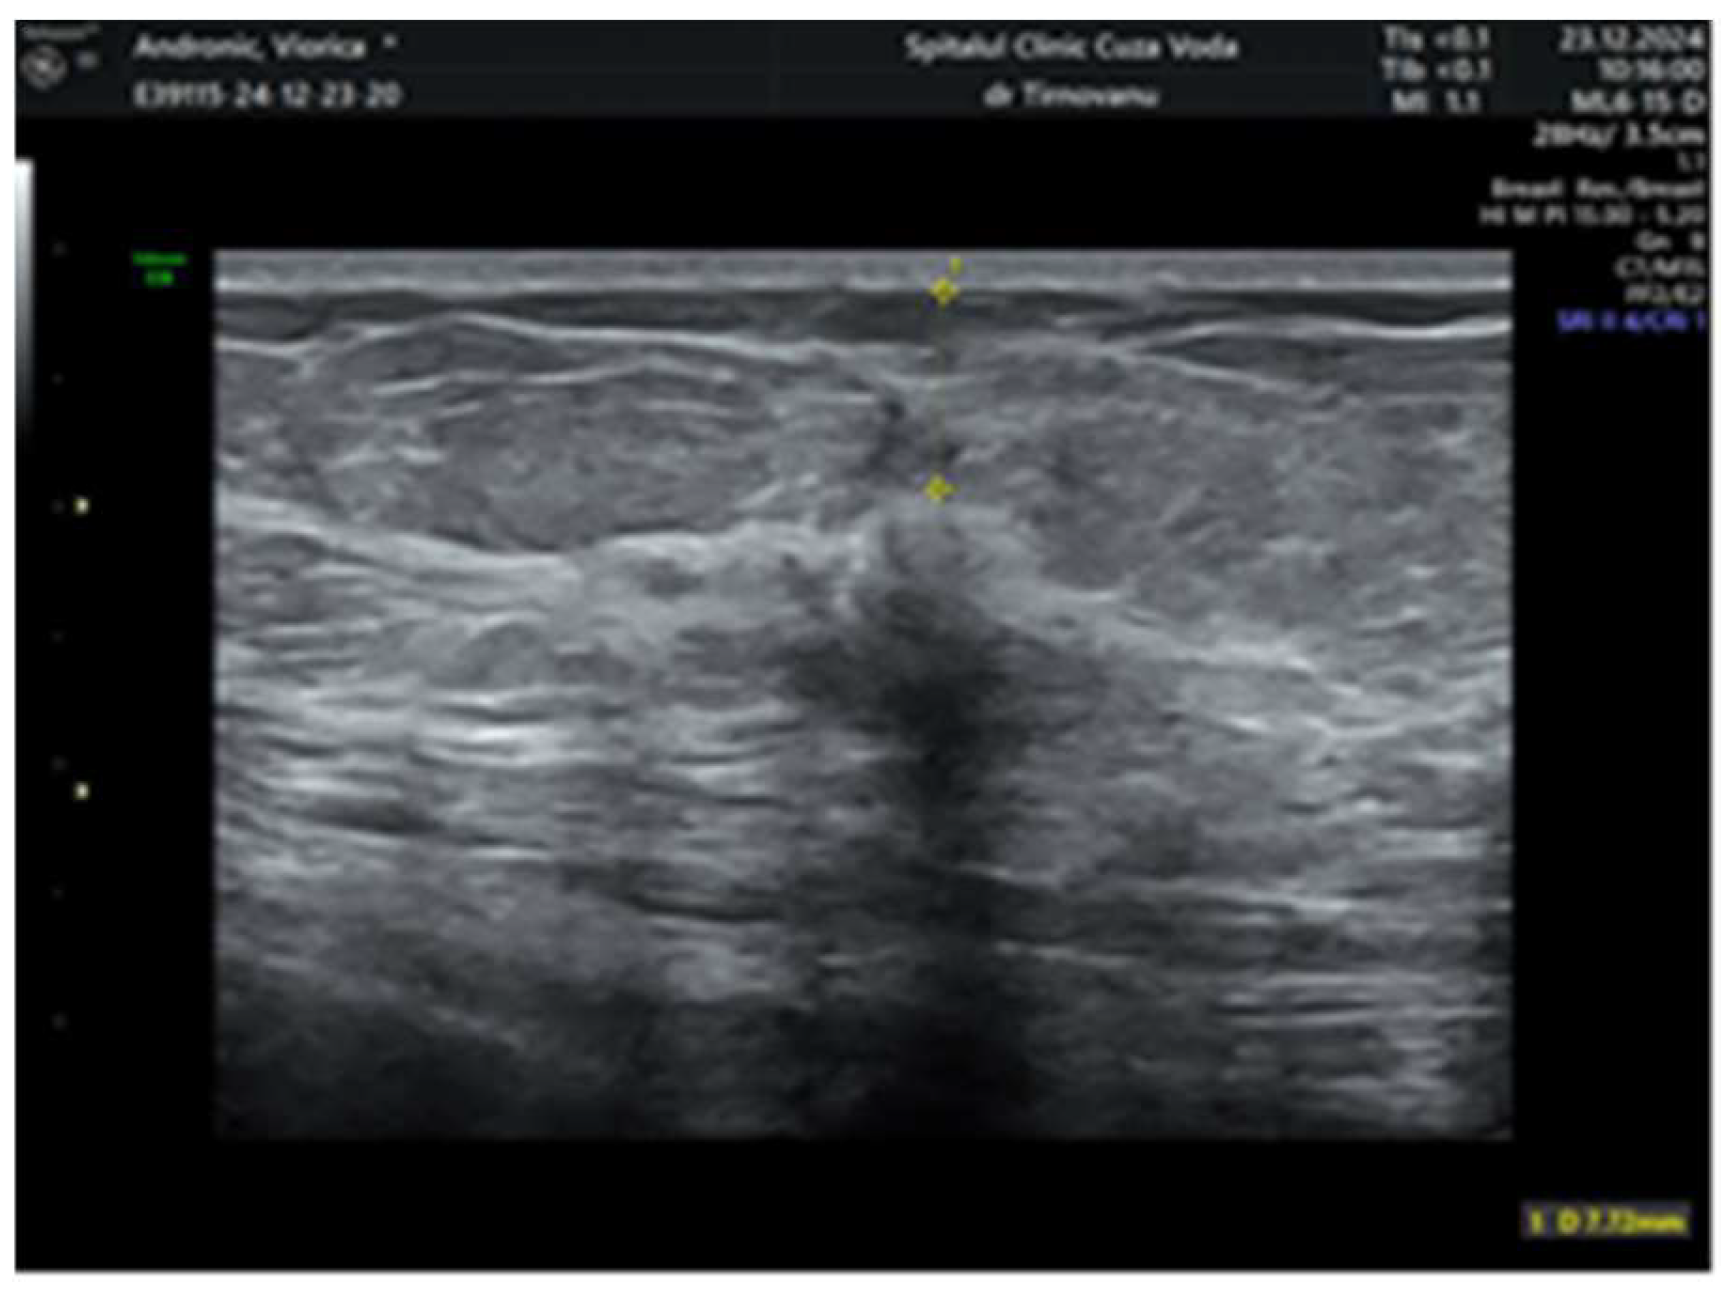

2. Case Report